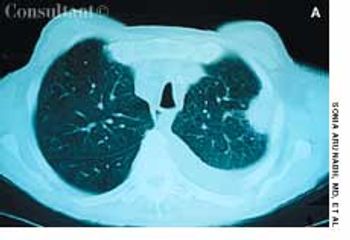

A 64-year-old woman with a history of diabetes, hypertension, and lymphoma was admitted to the hospital with a dull headache, conjunctival congestion, and slight dyspnea. Her pulse rate was 96 beats per minute; blood pressure, 146/68 mm Hg; and respiration rate, 22 breaths per minute. She also had increased jugular venous distention; cardiovascular and chest examination findings were normal. Edema of both arms and dilated blood vessels on the anterior chest wall were noted.